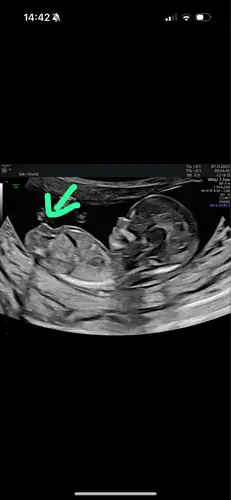

Ik vind het zo knap dat mensen hier wijs uit komen, ik kom er zelf maar niet uit, maar ben stiekem ook wel benieuwd of onze 2de een jongen of meisje is, kan iemand helpen? 😊

Alvast bedankt !

Duidelijk meisje!